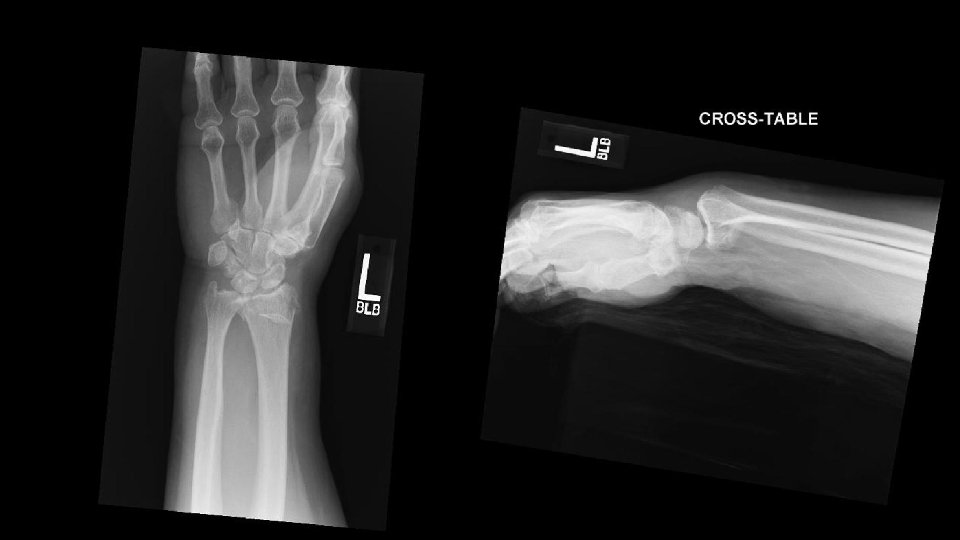

FX RADIOCUBITAL DISTAL FRACTURA DE SMITH Colles invertida. Poco frecuente. Jóvenes Caida sobre el dorso de la mano o por un golpe directo en flexion palmar. • Fracturas metafisarias o epifisarias del radio distal con desplazamiento, angulación e impactacion volar del fragmento distal. • •

FX RADIOCUBITAL DISTAL CLASIFICACIÓN DE LAS FRACTURAS DE SMITH